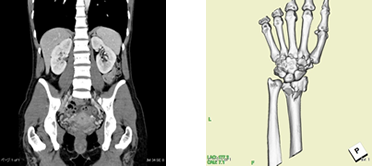

CT検査

CTとは、ComputedTomography(コンピューター断層撮影)の略語です。X線を利用して、体内の情報を集め計算により人体の横断像 (輪切り)を撮影することが出来ます。検査時間は、検査の内容や部位によって異なりますが約5~20分程度の短時間ですみます。また、造影剤を使用することにより、あらゆる血管(脳・胸部・腹部・上下肢血管)や腫瘍などの撮影が可能となります。

さらに、CTで収集したデータを用い画像処理ワークステーションを使用して様々な方向の断層像や、骨や血管などの3D画像を作成することも可能です。(下記の心臓CT検査やCTコロノグラフィー検査もワークステーション処理によるものです)

CTコロノグラフィー検査

CTコロノグラフィー検査とは、CTを用いた大腸検査の総称です。拡張や鎮痙剤で腸管の蠕動運動の抑制を行い、注腸X線造影検査や大腸内視鏡と同様の前処置をしたうえで撮影し専用の大腸解析ソフトを用いて、様々な再構成画像を作成し評価します。